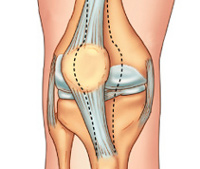

Вывих коленного сустава — это смещение суставных поверхностей костей, образующих коленный сустав, относительно друг друга. В коленном суставе может возникать два вида вывихов: смещение большеберцовой кости относительно бедренной и смещение надколенника относительно большеберцовой и бедренной костей. Патология проявляется резкой болью, отеком и деформацией зоны повреждения. Движения в суставе невозможны. Лечение — немедленное вправление с последующей иммобилизацией. При вывихах большеберцовой кости часто требуются восстановительные операции в отдаленном периоде.

Вывих коленного сустава — патологическое состояние, при котором суставные поверхности костей смещаются и перестают быть конгруэнтными. Под данным термином в травматологии и ортопедии понимают два вида вывихов, значительно различающихся по тяжести: вывих большеберцовой кости и вывих надколенника. Вывихи большеберцовой кости возникают чрезвычайно редко, являются результатом значительного травматического воздействия и нередко влекут за собой тяжелые отдаленные последствия (болтающийся сустав, артроз). Вывих надколенника — достаточно распространенная травма, прогноз при этой патологии благоприятен.

Бедренная и большеберцовая кости соединяются между собой, формируя коленный сустав, который имеет капсулу и укреплен мощными связками. Между суставными концами костей находятся эластичные прокладки — мениски. Значительное смещение суставных поверхностей костей возможно только при высокоэнергетических травмах, сопровождающихся нарушением целостности множества элементов сустава, поэтому вывихи коленного сустава сочетаются с разрывами связок, повреждениями менисков, переломами эпифизарной и метафизарной зон.

Надколенник располагается спереди, является сесамовидной костью (окостеневшей частью сухожилия), не соединяется с другими костями, сверху фиксируется сухожилиями четырехглавой мышцы бедра, снизу — собственной связкой надколенника. При вывихе надколенник может смещаться вбок (кнутри или кнаружи), разворачиваться вокруг своей оси или вклиниваться в суставную щель между большеберцовой и бедренной костями. Основные структуры колена при этом зачастую остаются неповрежденными или повреждаются незначительно.